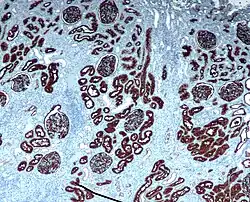

Immunohistochemia – jest to metoda wykrywania rozmaitych substancji antygenowych w skrawkach mikroskopowych, stosowana w histopatologii i histologii. Polega na zastosowaniu przeciwciała skierowanego przeciwko poszukiwanym składnikom preparatu a następnie systemu detekcji, tworzącego barwną, nierozpuszczalną substancję, widoczną w mikroskopie. Do związków chemicznych stosowanych do lokalizacji stosowanych w tej metodzie przeciwciał należą:

Metoda ta znajduje zastosowanie w diagnostyce różnicowej chorób, szczególnie nowotworów złośliwych.